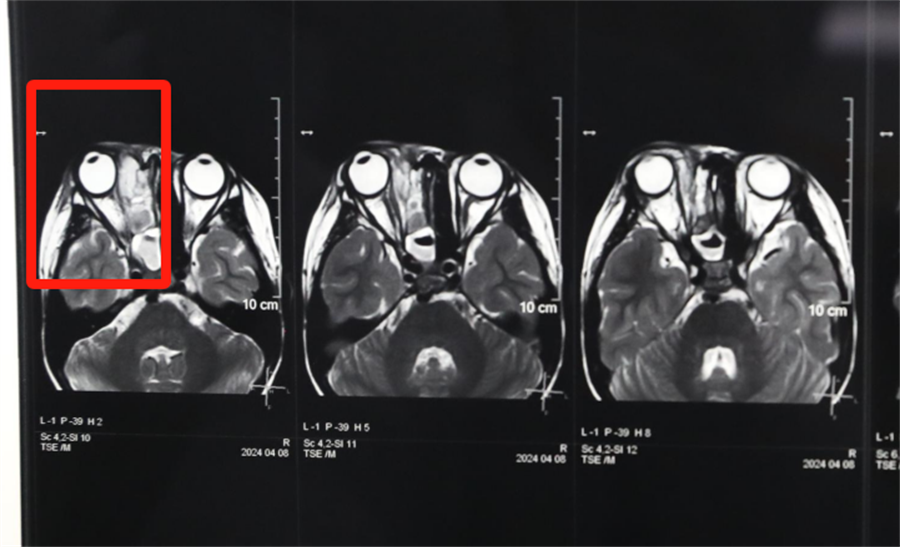

经眼科、耳鼻喉科联合会诊,医生发现孩子是因为患了急性鼻窦炎,导致右眼急性细菌感染,确诊为“右侧眶蜂窝织炎、眶内脓肿”。考虑到此病进展较快,可能导致视力下降甚至失明,耳鼻喉科立即将患儿收治入院。静脉输液、对症支持治疗、密切监测视力变化,一切有条不紊。入院第2天,孩子自觉右眼视力下降明显,眼科紧急会诊发现,其右眼视力从患病前的1.0下降到0.4。

3岁男童小壮(化名)在出生后就出现左侧鼻子堵,一直流白色胶冻样鼻涕。三年来,家长反复带他去成人医院看病,每次都诊断为鼻炎,怎么用药都没治好,这也就成了一家人的烦心事。凑巧的是,前几天孩子把一粒黄豆塞进了左侧鼻孔,家长赶忙带他来到啪啪网 ,医生顺利取出了黄豆,并做了儿童电子鼻咽镜检查,这才发现了孩子左侧鼻子一直堵塞的真正原因——先天性后鼻孔闭锁。

孩子左侧鼻腔3年来没有通气,鼻腔的发育受到了严重影响,甚至部分结构出现了一定程度的萎缩,并患有严重的鼻窦炎。杨小健副院长认真分析了孩子的病情,认为应该尽快手术治疗。